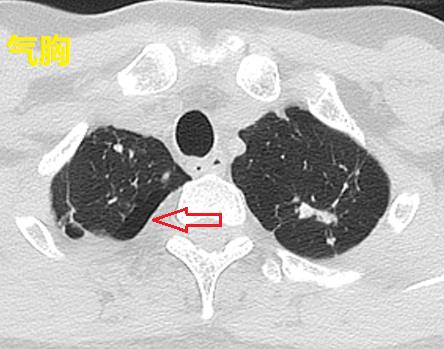

这个引流管放进去,啥都没有引流出来,还导致了少量气胸。

图06